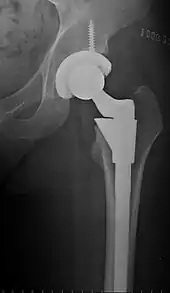

Implants

The prosthetic implant used in hip replacement consists of three parts: the acetabular cup, the femoral component, and the articular interface. Options exist for different people and indications. The evidence for a number of newer devices is not very good, including: ceramic-on-ceramic bearings, modular femoral necks, and uncemented monoblock cups.[89]

Acetabular cup

The acetabular cup is the component which is placed into the acetabulum (hip socket). Cartilage and bone are removed from the acetabulum and the acetabular cup is attached using friction or cement. Some acetabular cups are one piece, while others are modular. One-piece (monobloc) shells are either ultra-high-molecular-weight polyethylene or metal, they have their articular surface machined on the inside surface of the cup and do not rely on a locking mechanism to hold a liner in place. A monobloc polyethylene cup is cemented in place while a metal cup is held in place by a metal coating on the outside of the cup. Modular cups consist of two pieces, a shell and liner. The shell is made of metal; the outside has a porous coating while the inside contains a locking mechanism designed to accept a liner. Two types of porous coating used to form a friction fit are sintered beads and a foam metal design to mimic the trabeculae of cancellous bone and initial stability is influenced by under-reaming and insertion force.[90] Permanent fixation is achieved as bone grows onto or into the porous coating. Screws can be used to lag the shell to the bone providing even more fixation. Polyethylene liners are placed into the shell and connected by a rim locking mechanism; ceramic and metal liners are attached with a Morse taper.

Articular interface

The articular interface is not part of either implant, rather it is the area between the acetabular cup and femoral component. The articular interface of the hip is a simple ball and socket joint. Size, material properties and machining tolerances at the articular interface can be selected based on patient demand to optimise implant function and longevity whilst mitigating associated risks. The interface size is measured by the outside diameter of the head or the inside diameter of the socket. Common sizes of femoral heads are 28 mm (1.1 in), 32 mm (1.3 in) and 36 mm (1.4 in). While 22.25 mm (7⁄8 in) was common in the first modern prostheses, now even larger sizes are available from 38 to over 54 mm. Larger-diameter heads lead to increased stability and range of motion whilst lowering the risk of dislocation. At the same time they are also subject to higher stresses such as friction and inertia. Different combinations of materials have different physical properties which can be coupled to reduce the amount of wear debris generated by friction. Typical pairings of materials include metal on polyethylene (MOP), metal on crosslinked polyethylene (MOXP), ceramic on ceramic (COC), ceramic on crosslinked polyethylene (COXP), and metal on metal (MOM). Each combination has different advantages and disadvantages.[91]

Post-operative projectional radiography is routinely performed to ensure proper configuration of hip prostheses.